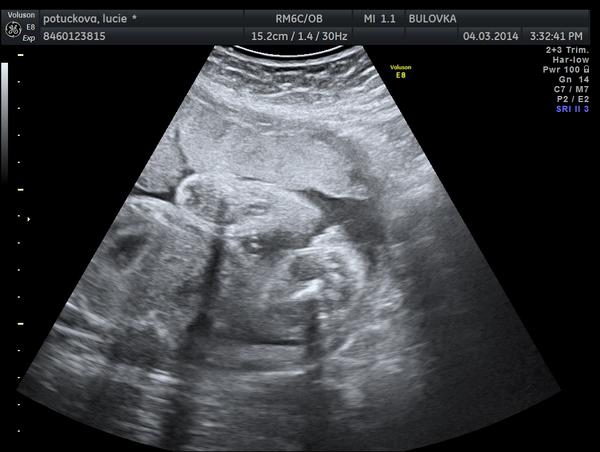

Je to holčička nebo chlapeček? Foto ultrazvuku

Dobré ráno, tak se taky přidávám se svou troškou do mlýna - co myslíte, holčička nebo chlapeček? 😀